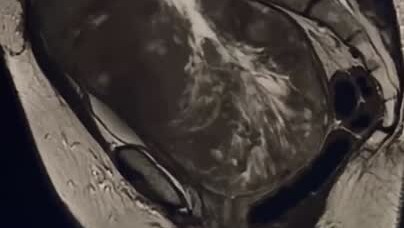

Дорогие друзья, хочу рассказать вам историю моей пациентки, которой нам предстоит удалить огромное новообразование малого таза.